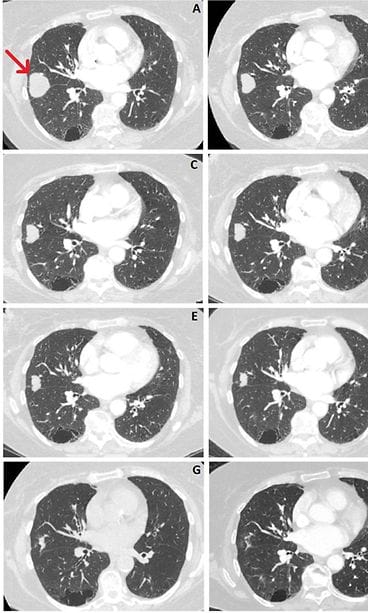

Potilaan tilannetta seuraavat lääkärit eivät tienneet asiasta, mutta yllätyksekseen he havaitsivat, että kasvain alkoi kutistua. Nainen paljasti lääkäreille vuonna 2019, että hän oli aloittanut CBD-öljyn käytön pian diagnoosinsa jälkeen. Helmikuuhun 2021 mennessä syöpäkasvain oli kutistunut yli kolme senttiä eli neljännekseen alkuperäisestä koostaan. Ainoa naisen tekemä elämäntapamuutos oli CBD-öljyn käytön aloittaminen.